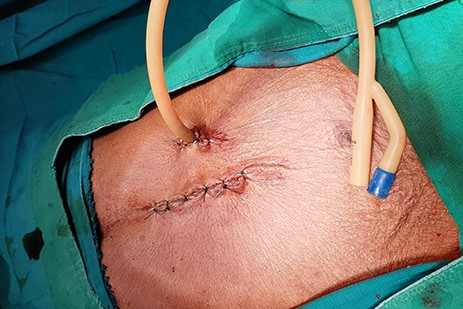

The patient was scheduled for GFT insertion. Under aseptic technique, with the patient in supine position, 24 Fr urinary catheter as an improvised GFT was inserted in Stamm manner, haemostasis achieved, abdomen closed in layers and dressed (Fig. 9). There was no ascites and mesenteric lymph nodes were not palpable. After the procedure the patient was discharged home on the second day with analgesics and was booked for a surgical outpatient clinic appointment after 2 weeks.

24Fr urinary catheter as an improvised gastrostomy feeding tube.